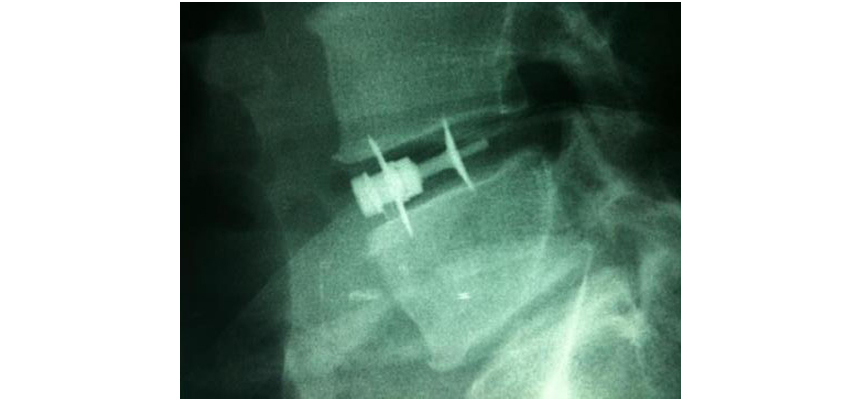

Alif Double Locking Cage A2L

Alif Double Locking Cage A2L® is part of a wide range of radiolucent cages equipped with a unique patented locking double blade mechanism, offering a variety of alternatives for the anterior surgery of lumbo-sacral spine.

The immediate and secondary stability of the cage is supported by simple rotation of instrument (UNIQUE CONCEPTION) which makes the two titanium blades penetrate into vertebral plates as soon as the instrument is turned.

Easiest locking mechanism : To lock the cage, just turn the instrument after insertion.